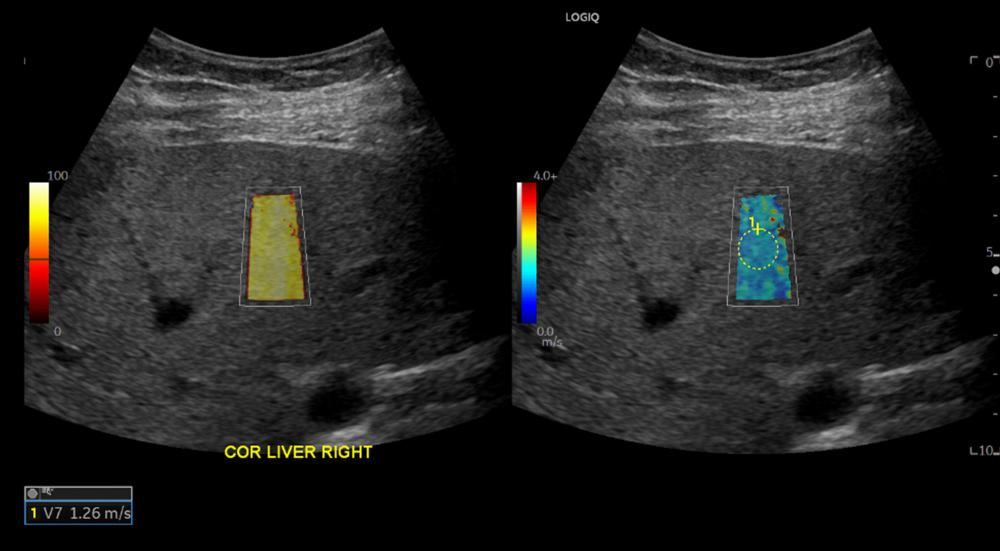

Figure 2. A 57-year-old female without a history of positive COVID-19 test before the date of ultrasound shear wave elastography. The shear wave speed of 1.26 m/s corresponds to Young’s modulus of 4.76 kPa which indicates normal liver stiffness.

High-res (TIF) version